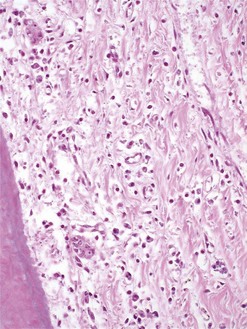

Fig. 10.13 Decalcified histological image of the base of a valve CT diastema showing erosion and hyperplasia of the gingiva in the interproximal space. (Original magnification ×100.)

(Courtesy of Alistair Cox and Sionagh Smith.)